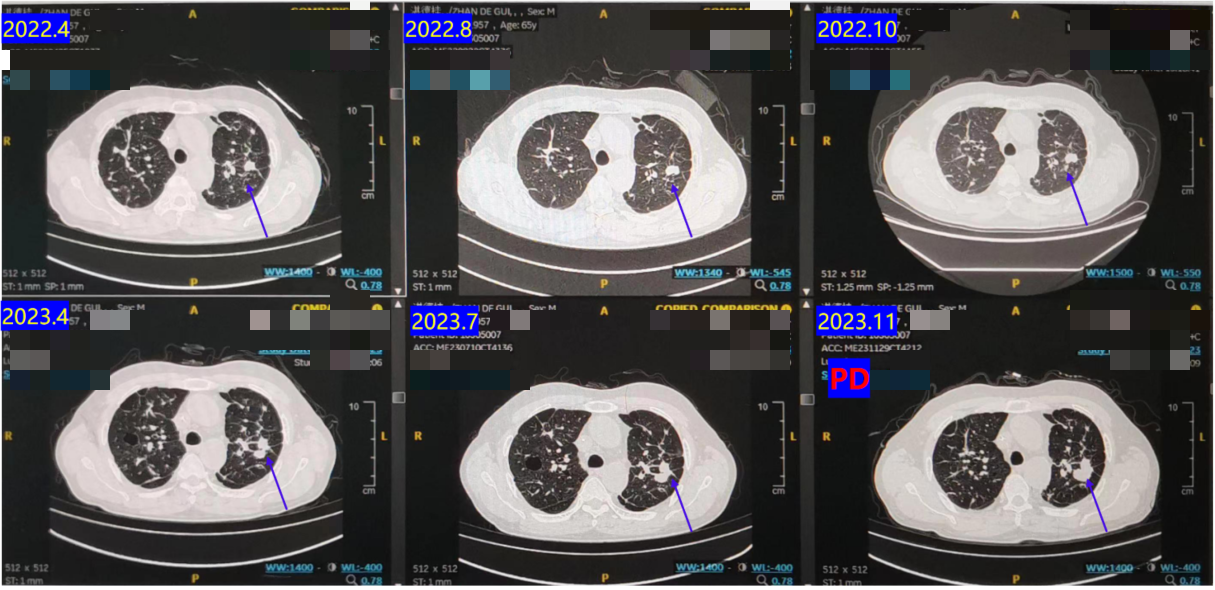

2021.12-2023.12:调整方案为 西达本胺 + 贝伐珠单抗 维持治疗,进行16周期。

长期随访CT显示,肺部病灶持续维持在低水平,疗效评价持续PR。

2023.11复查CT提示胸部病灶较前增大(PD)(图9)。PFS长达32个月!